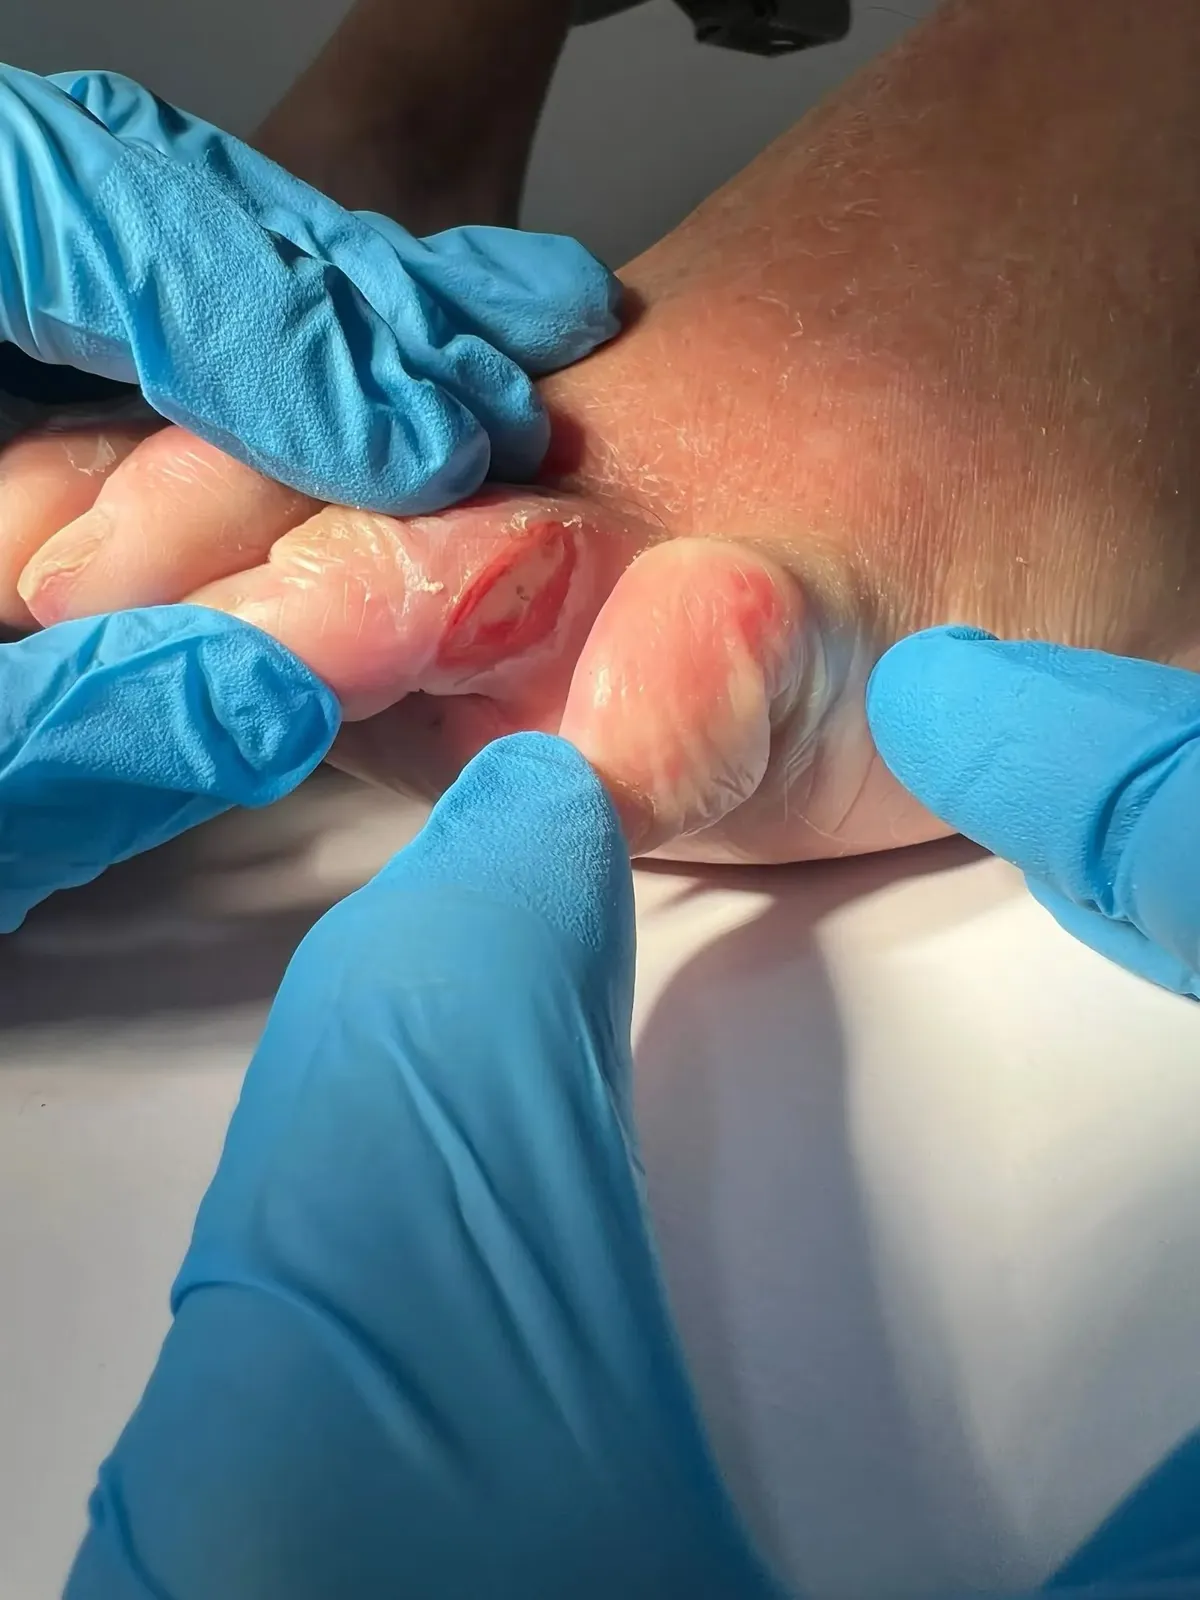

El paciente: Varón de 84 años con diversas patologías crónicas, que acudió a nuestra consulta por un dolor intenso entre el 4º y 5º dedo que empeoraba cada día. No recordaba ningún golpe concreto, pero cada vez le costaba más caminar y calzarse.

Lo que encontramos: Durante la exploración observamos una úlcera interdigital de tamaño importante, con la piel muy macerada alrededor, enrojecimiento e inflamación que se extendían al dorso del pie. Dada la intensidad del dolor y el perfil del paciente, realizamos una radiografía que reveló alteración ósea asociada.

Esto no era una simple rozadura. Lo que parecía una herida menor tenía afectación en profundidad.

Nuestro abordaje: Diseñamos un tratamiento conservador estructurado y estrechamente controlado:

- Limpieza exhaustiva y tratamiento local de la úlcera

- Control del exceso de humedad interdigital

- Descarga mecánica del espacio entre los dedos

- Manejo del dolor adaptado a su estado general

- Seguimiento clínico estrecho con revisiones periódicas

El resultado: Con el tratamiento instaurado y el seguimiento continuado, la lesión mostró una evolución favorable, con disminución progresiva del dolor y mejora del estado del tejido.